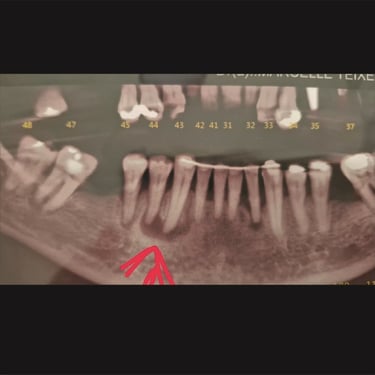

CASOS CLÍNICOS ENDO

Abaixo você encontra fotos de alguns dos tratamentos realizados.